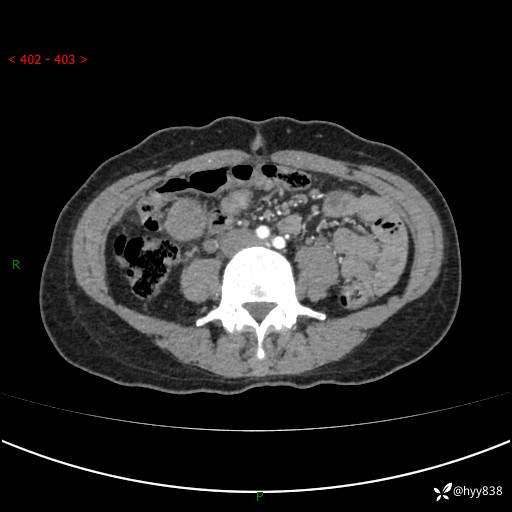

年轻女性,发现腹腔肿物1周。圆圆的肿物,诊断有难度---结果公布~

现病史:患者自诉于1周前无明显诱因出现剑突下间断性隐痛,尚可忍受,不向其它部位放射,无恶心呕吐、腹泻便秘等不适,于当地市第二人民医院就诊,行CT结果示:1.右中腹占位,间叶组织来源可能2.小肠梗阻3.盆腔积液4.腹腔积液5.副脾6.肝囊肿;于荆州二医行抗炎,抑酸,护胃,补液等对症支持治疗;患者病情好转,今为求进一步诊治,遂来我院门诊就诊,门诊以“腹腔肿瘤”收入院。 起病以来,患者精神、睡眠、饮食一般,大小便正常,近期体力体重无明显改变。

腹部CT增强(外院平扫)